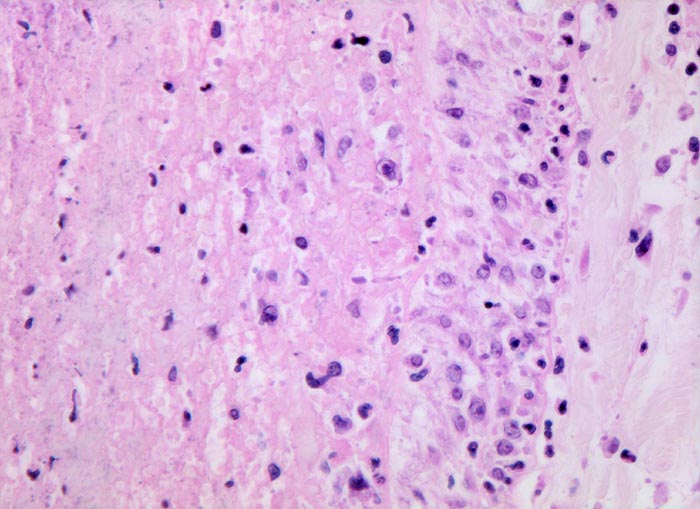

• Alveolen gefüllt mit zerfallenden Erythrozyten, Kerntrümmern und Fibrin.

• Abgeblasste Zellkerne in der Nekrosezone.

• Pulmonalarterienast mit nicht wandhaftendem Thrombembolus am Rand des Infarktes.